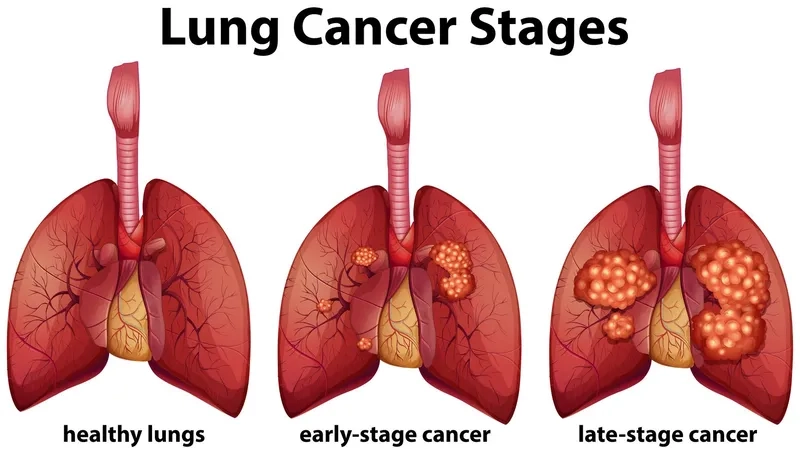

- As the cancer progresses through different lung cancer stages, symptoms may include bone pain, headaches, and shortness of breath.

Image of the disease Lung Cancer - and other variables